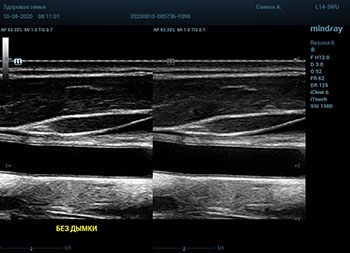

Ультразвуковое оборудование не отстает от современно тренда. В приборах серии Resona, компании Mindray, появилась новая функция постобработки изображения. Имя ей Dehaze. В переводе на наш родной язык – удаление дымки или рассеивание тумана. Инструмент позволяет корректировать интенсивность тумана или дымки. При этом сохраняется общий контраст и детализация картинки. Dehaze также позволяет проявлять детали снимка в гиперэхогенных зонах и снимать артефакты при чрезмерном усилении.

Готовый снимок или видео петля в формате DICOM несет в себе полное нативное изображение. Прибор позволяет, подобно легендарному фотошопу, удалить лишний «туман». Гиперэхогенный диффузный «засвет» изображения, из-за повышенного общего усиления, часто вредит обследованию. Однако без него некоторые вещи не видны. Показать гипоэхогенные участки и скрыть эхогенную дымку и позволяет Dehaze.

Всё что требуется от доктора – нажать кнопку или повернуть ручку. Мгновенная оптимизация. Мгновенно чистое изображение.